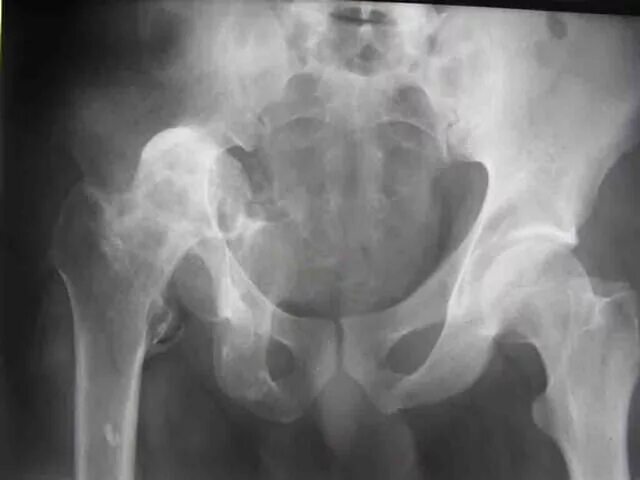

Вывих тазобедренного у взрослых